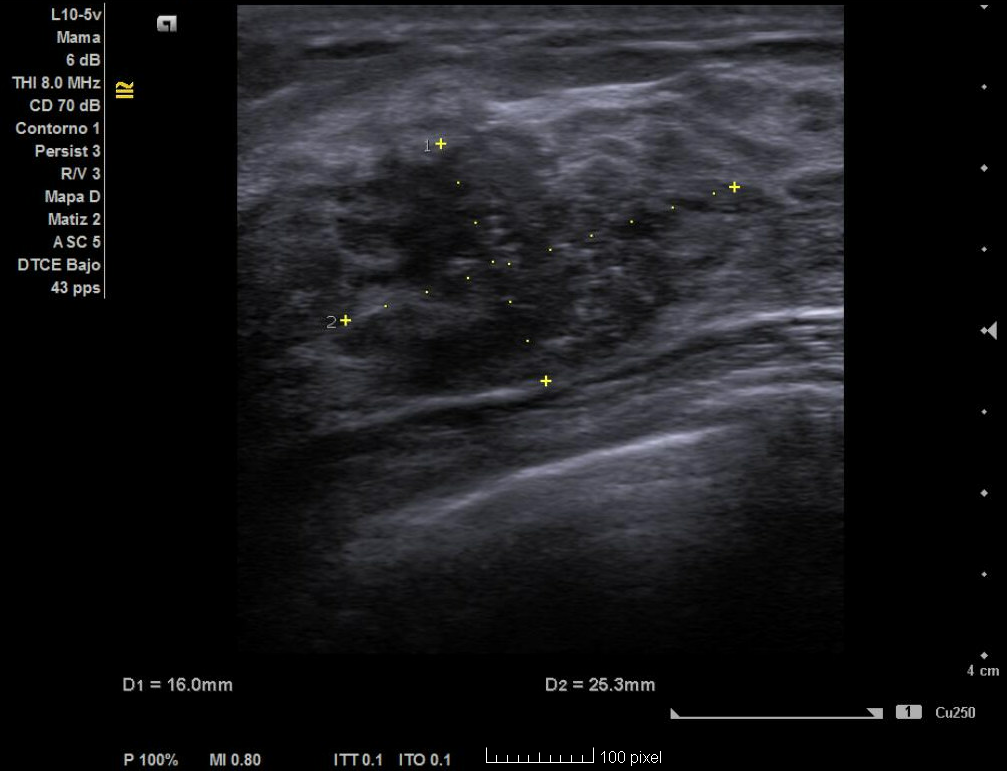

Ecografía no reglada en AP: nódulo de 2,3 cm x 1,4 cm con bordes irregulares no bien delimitados, hipoecoica, heterogénea en donde hay zonas espiculadas, con microcalcificaciones y captación Doppler en interior.